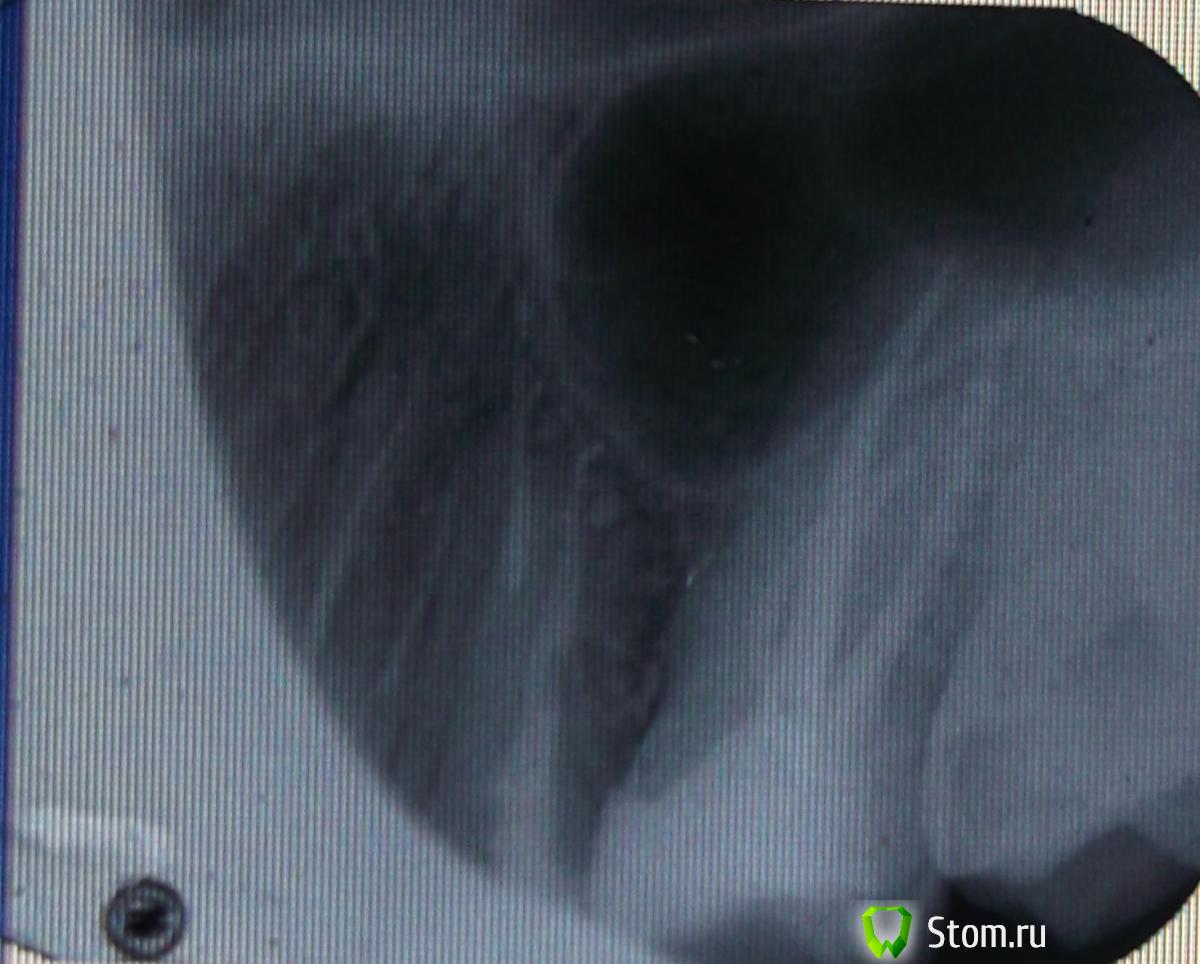

FBR Опубликовано 31 марта, 2012 Поделиться Опубликовано 31 марта, 2012 Удаление штифта. Восстановление культевой вкладкой. Металлокерамическая коронка. И обратите внимание на 16 зуб - его надо перелечивать, т.к. на медиальном корне- гранулема (воспаление). Ссылка на комментарий

FBR Опубликовано 31 марта, 2012 Поделиться Опубликовано 31 марта, 2012 (изменено) Удаление штифта. Восстановление культевой вкладкой. Металлокерамическая коронка. И обратите внимание на 16 зуб - его надо перелечивать, т.к. на медиальном корне- гранулема (воспаление).Пардон - на 46 зуб Изменено 31 марта, 2012 пользователем FBR Ссылка на комментарий